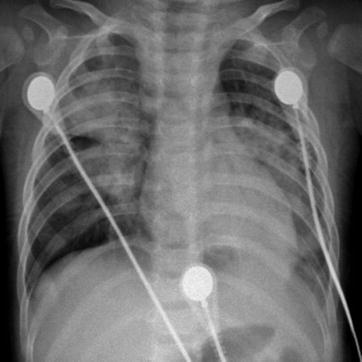

Fig. 23.18.

Pediatric measles complicated by pneumonia. (a) X-ray demonstrates multiple flakes of shadows in both lungs, blurry hilar shadow at both lungs, and blurry left costophrenic angle. (b) By reexamination after treatment for 1 day, X-ray demonstrates slightly extended range with shadows at both lungs. (c–h) By reexamination after treatment for 3 days, CT scanning demonstrates multiple large flakes of consolidation lesions in both lungs with inner air bronchus sign. (i) By reexamination after treatment for 8 days, the lesions are demonstrated to be absorbed and improved. X-ray demonstrates shrinkage of the range with lesions, decreased density of the lesions, quite clearly defined hilum at both lungs, and well-defined bilateral costophrenic angles